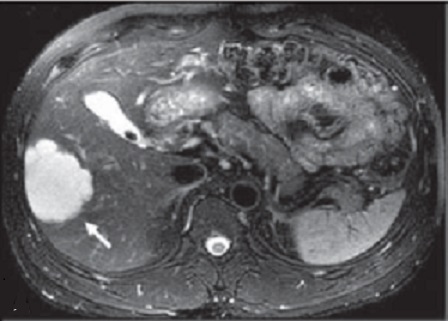

Image IRM

typique de hemangiome : Methode IRM est tres

performance de diagnostique hemagiome du foie : aspect

hyposignale en T1 et hypersignal en T2 . Cinetique de

rehaussement avec de contrast intraveineuse est resemble a

celle du TDM

Image hyposignal d'une

hemangiome du foie en coupe axiale de IRM a

travers du foie ponderee en T1 |

|

Image hypersignal

du mêm cas en coupe axiale de IRM a travers du

foie ponderee en T2 fat-sat |

Meme cas en IRM

ponderee en T2 non perfusion intraveineuse : Aspect du

tumeur est hypersignal ( fleche blanche ) |

Image IRM ponderation T1 plus contrast

intraveineuse . En phase de veine porte c'est image

de rehaussement progessive de peripherique vers le

central |